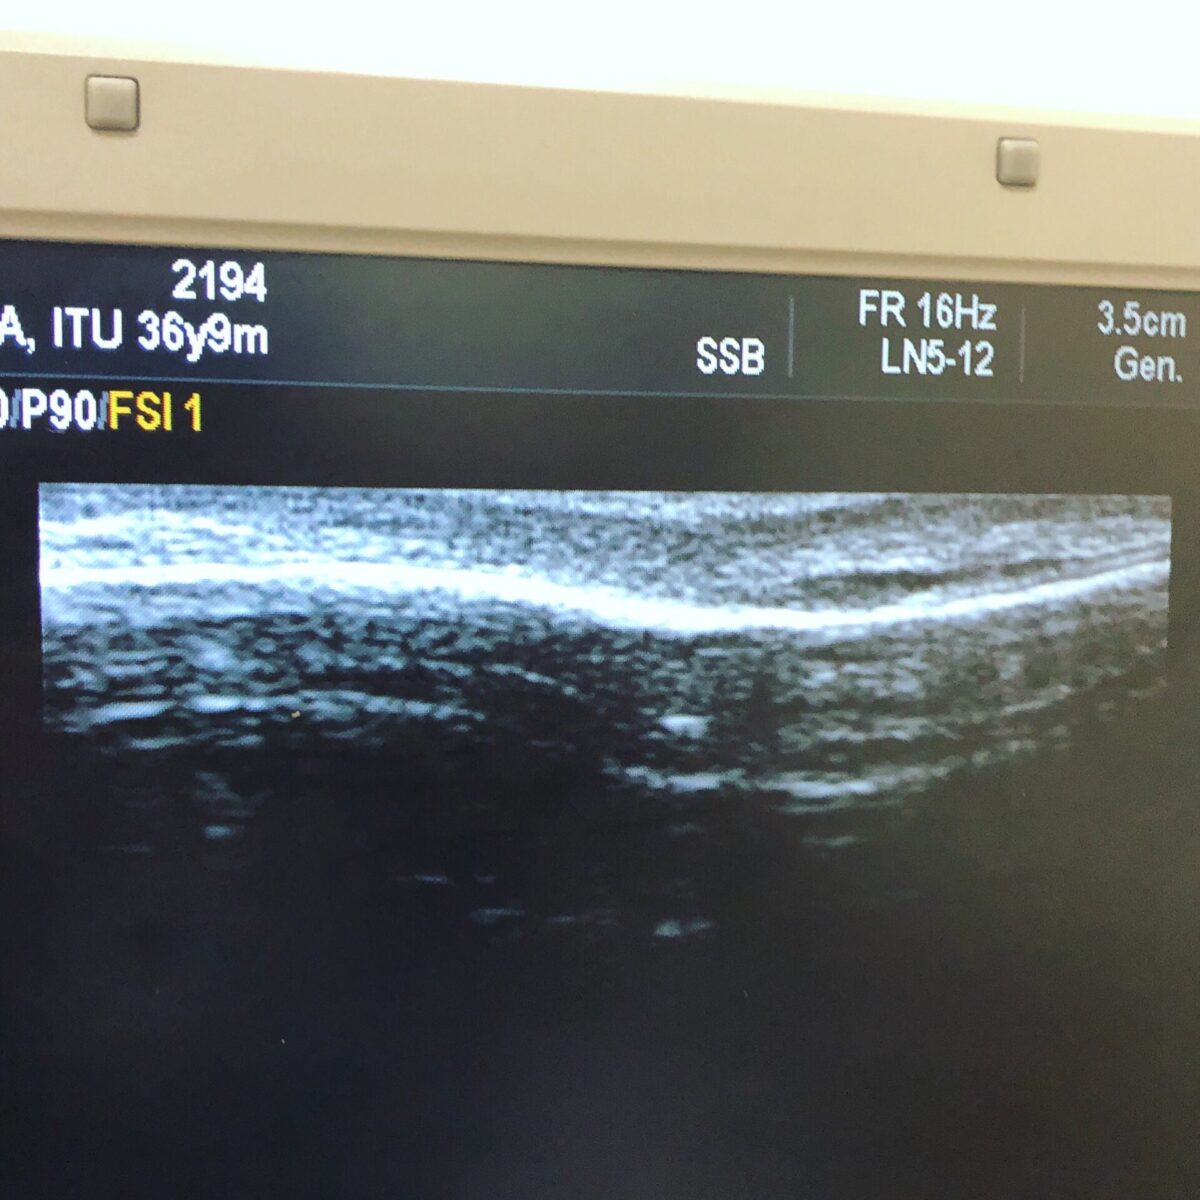

2018年11月に発覚して4ヶ月後に完治した左脚腓骨の疲労骨折した部分がなんかまた気になるのでエコー検査してもらった。

写真は左脚を前から見た輪郭で、写真右側がくるぶし。

疲労骨折した部分には集中的に骨が形成されるので盛り上がるし、当時触るだけでも分厚くなってるのがわかった。

普通と違うのは、

治る過程で形成された骨はそのうち削られて無くなるはずなのに、2年近く経った今も盛り上がったまんまだということ。

ストレスがかかり続けているからなのかどうなのかはわからない、とのこと。痛みがはっきり出ているわけではないのでとりあえず様子見。